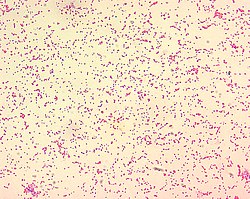

Brucella